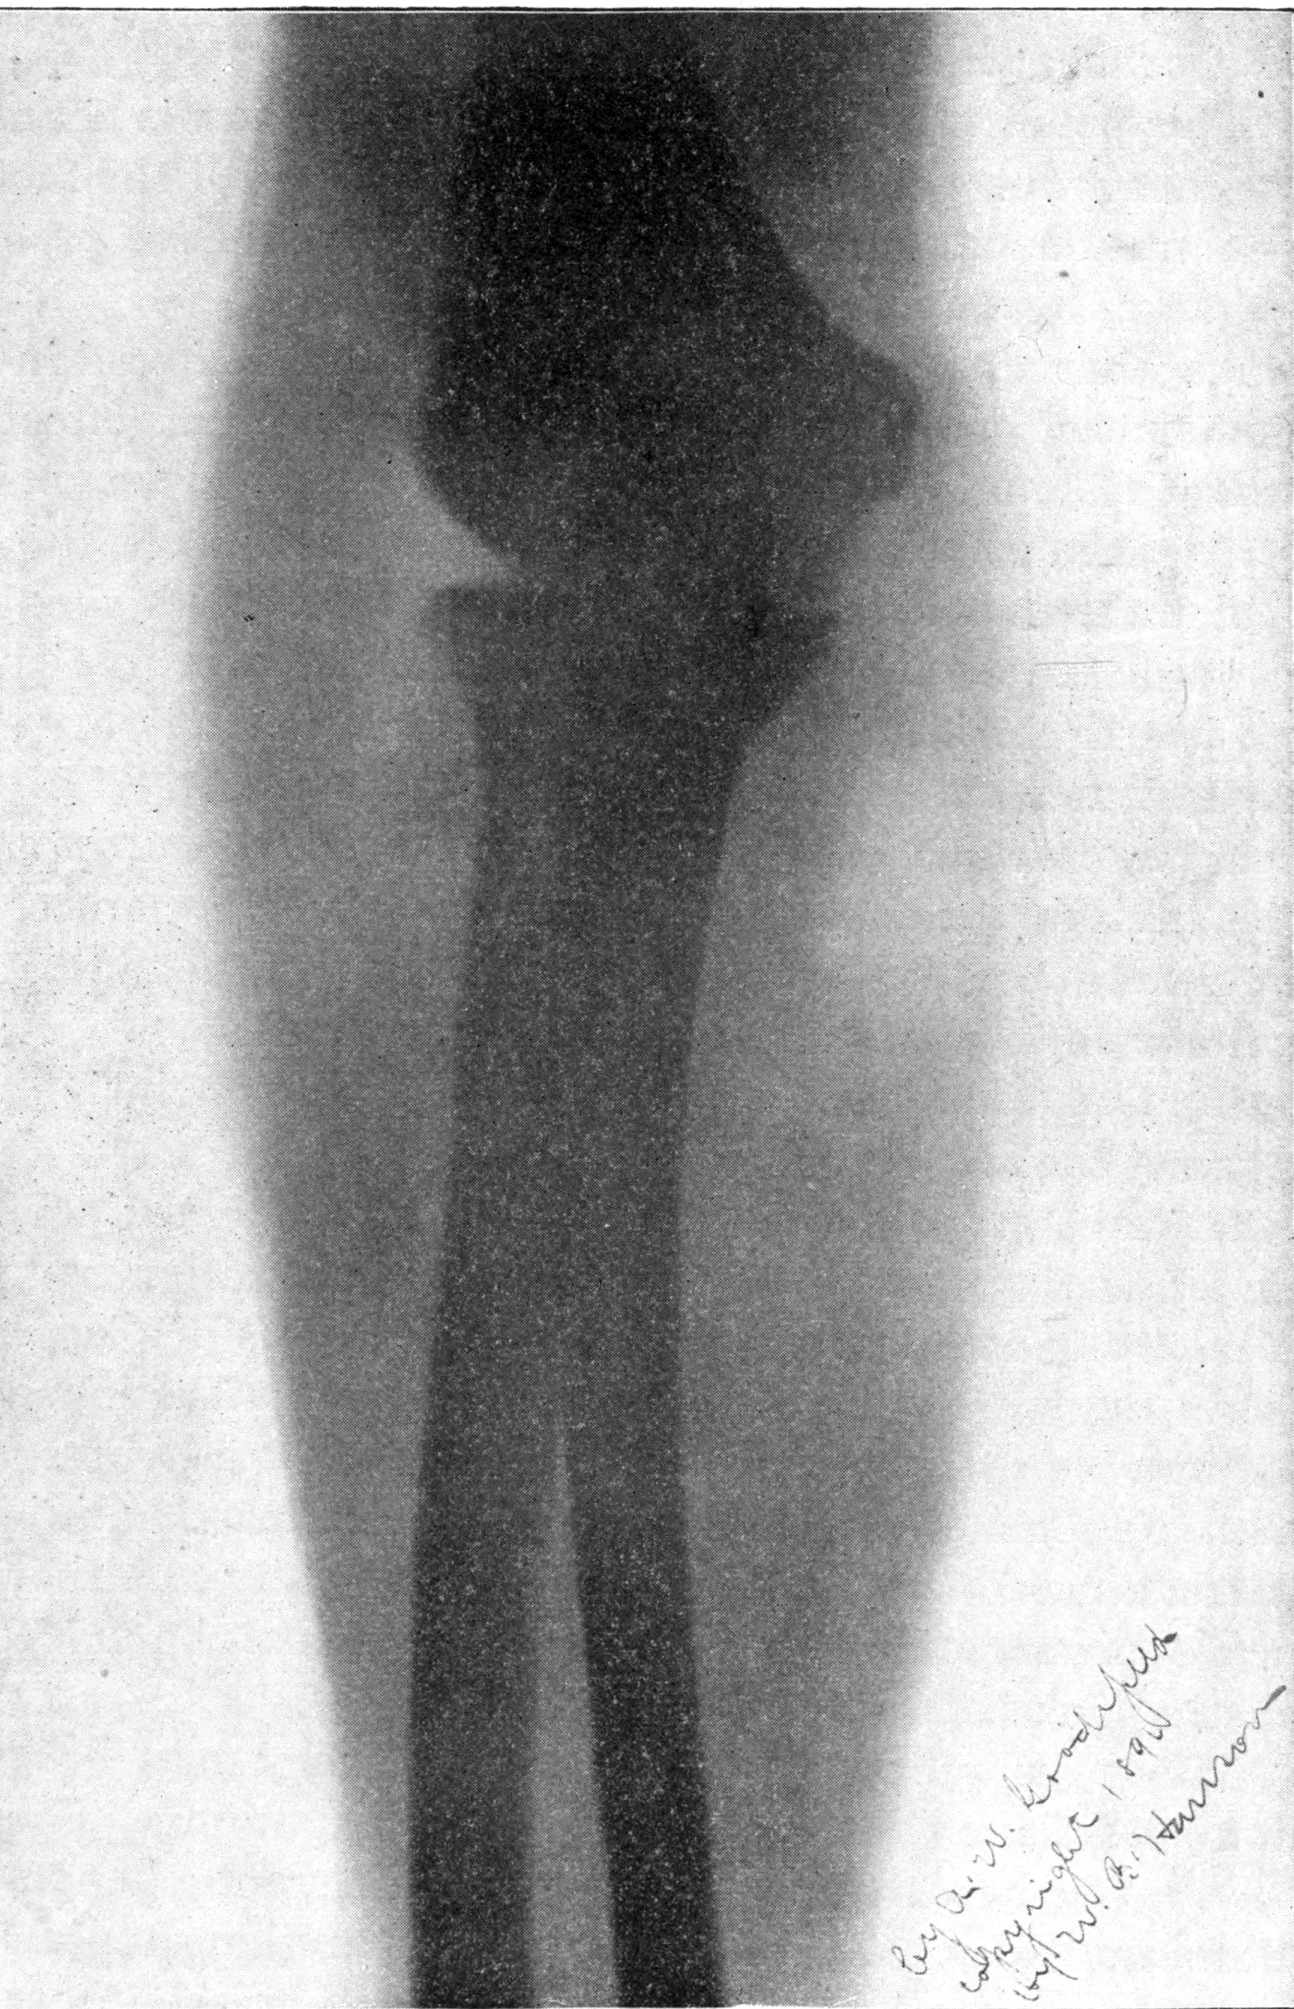

Fig. 2.—Broken Arm, Overlapping.

(Due to defective setting.)